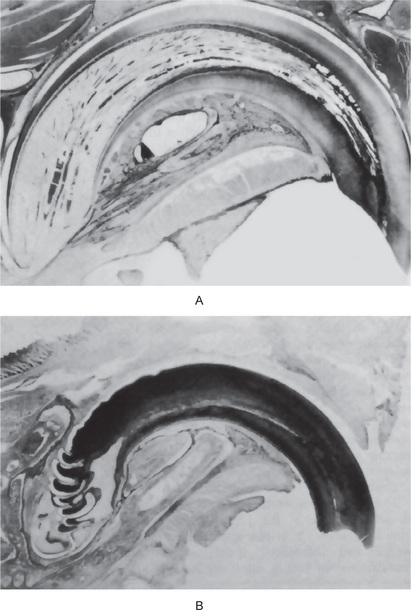

Characteristically, there is histologic evidence of widespread formation of globular, hypocalcified dentin, with clefts and tubular defects occurring in the region of the pulp horns. In addition, these pulp horns are elongated and extend high, often reaching nearly to the dentinoenamel junction. This may even be evident on the radiograph (Fig. 15-9). Because of these defects, there is commonly invasion of the pulp by microorganisms without demonstrable destruction of the tubular matrix. Following this, there is often periapical involvement of grossly normal-appearing deciduous or permanent teeth, followed by the development of multiple gingival fistulas. In addition to abnormal cementum, the lamina dura around the teeth is also reported to be frequently absent or poorly defined on the radiograph, and the alveolar bone pattern is often abnormal.

Figure 15-9 Vitamin D-resistant rickets in a boy six years of age.

The full mouth radiographs (A) show the wide root canals and pulp chambers. A ground section of an incisor tooth (B) shows the interglobular nature of the dentin. The deciduous molar (C) when split shows the relatively small quantity of dentin as well as the poor quality of the dentin. Note the connection between the pulp chamber and the occlusal surface of the tooth, a common finding in this disease, accounting for the frequent pulp infection and periapical involvement without the presence of a carious lesion. Courtesy of Dr SS Arnim